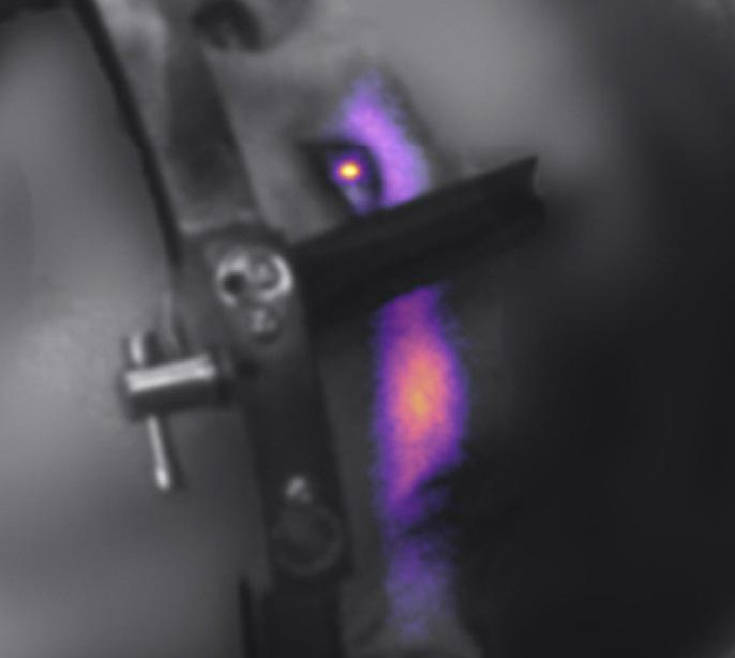

Ερευνητές του Norris Cotton Cancer Center χρησιμοποίησαν καινοτόμα συστήματα καταγραφής εικόνας για να καταγράψουν το φαινόμενο.

Όπως μας λένε στη μελέτη τους που δημοσιεύτηκε στο περιοδικό «International Journal of Radiation Oncology», πρόκειται για οφθαλμό ασθενούς που υποβλήθηκε σε ακτινοθεραπεία και η εικόνα καταγράφηκε σε πραγματικό χρόνο για πρώτη ποτέ φορά στην επιστήμη.